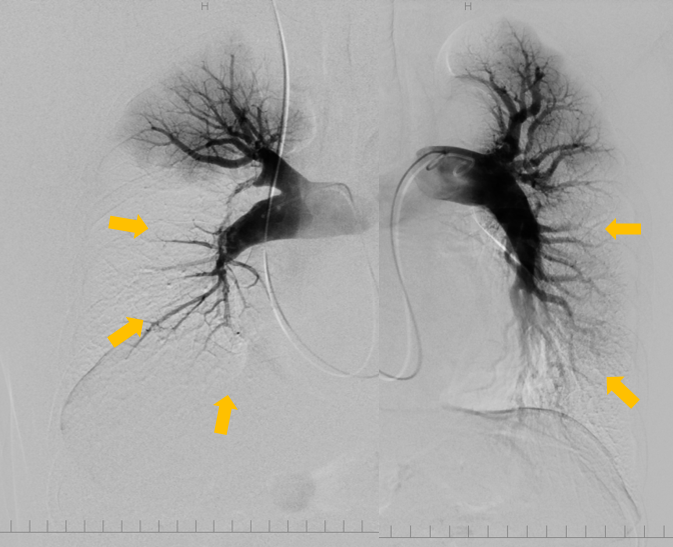

・肺動脈造影検査:【術前】矢印:主な狭窄や閉塞病変部位

【術後】矢印部分の血流改善を認める